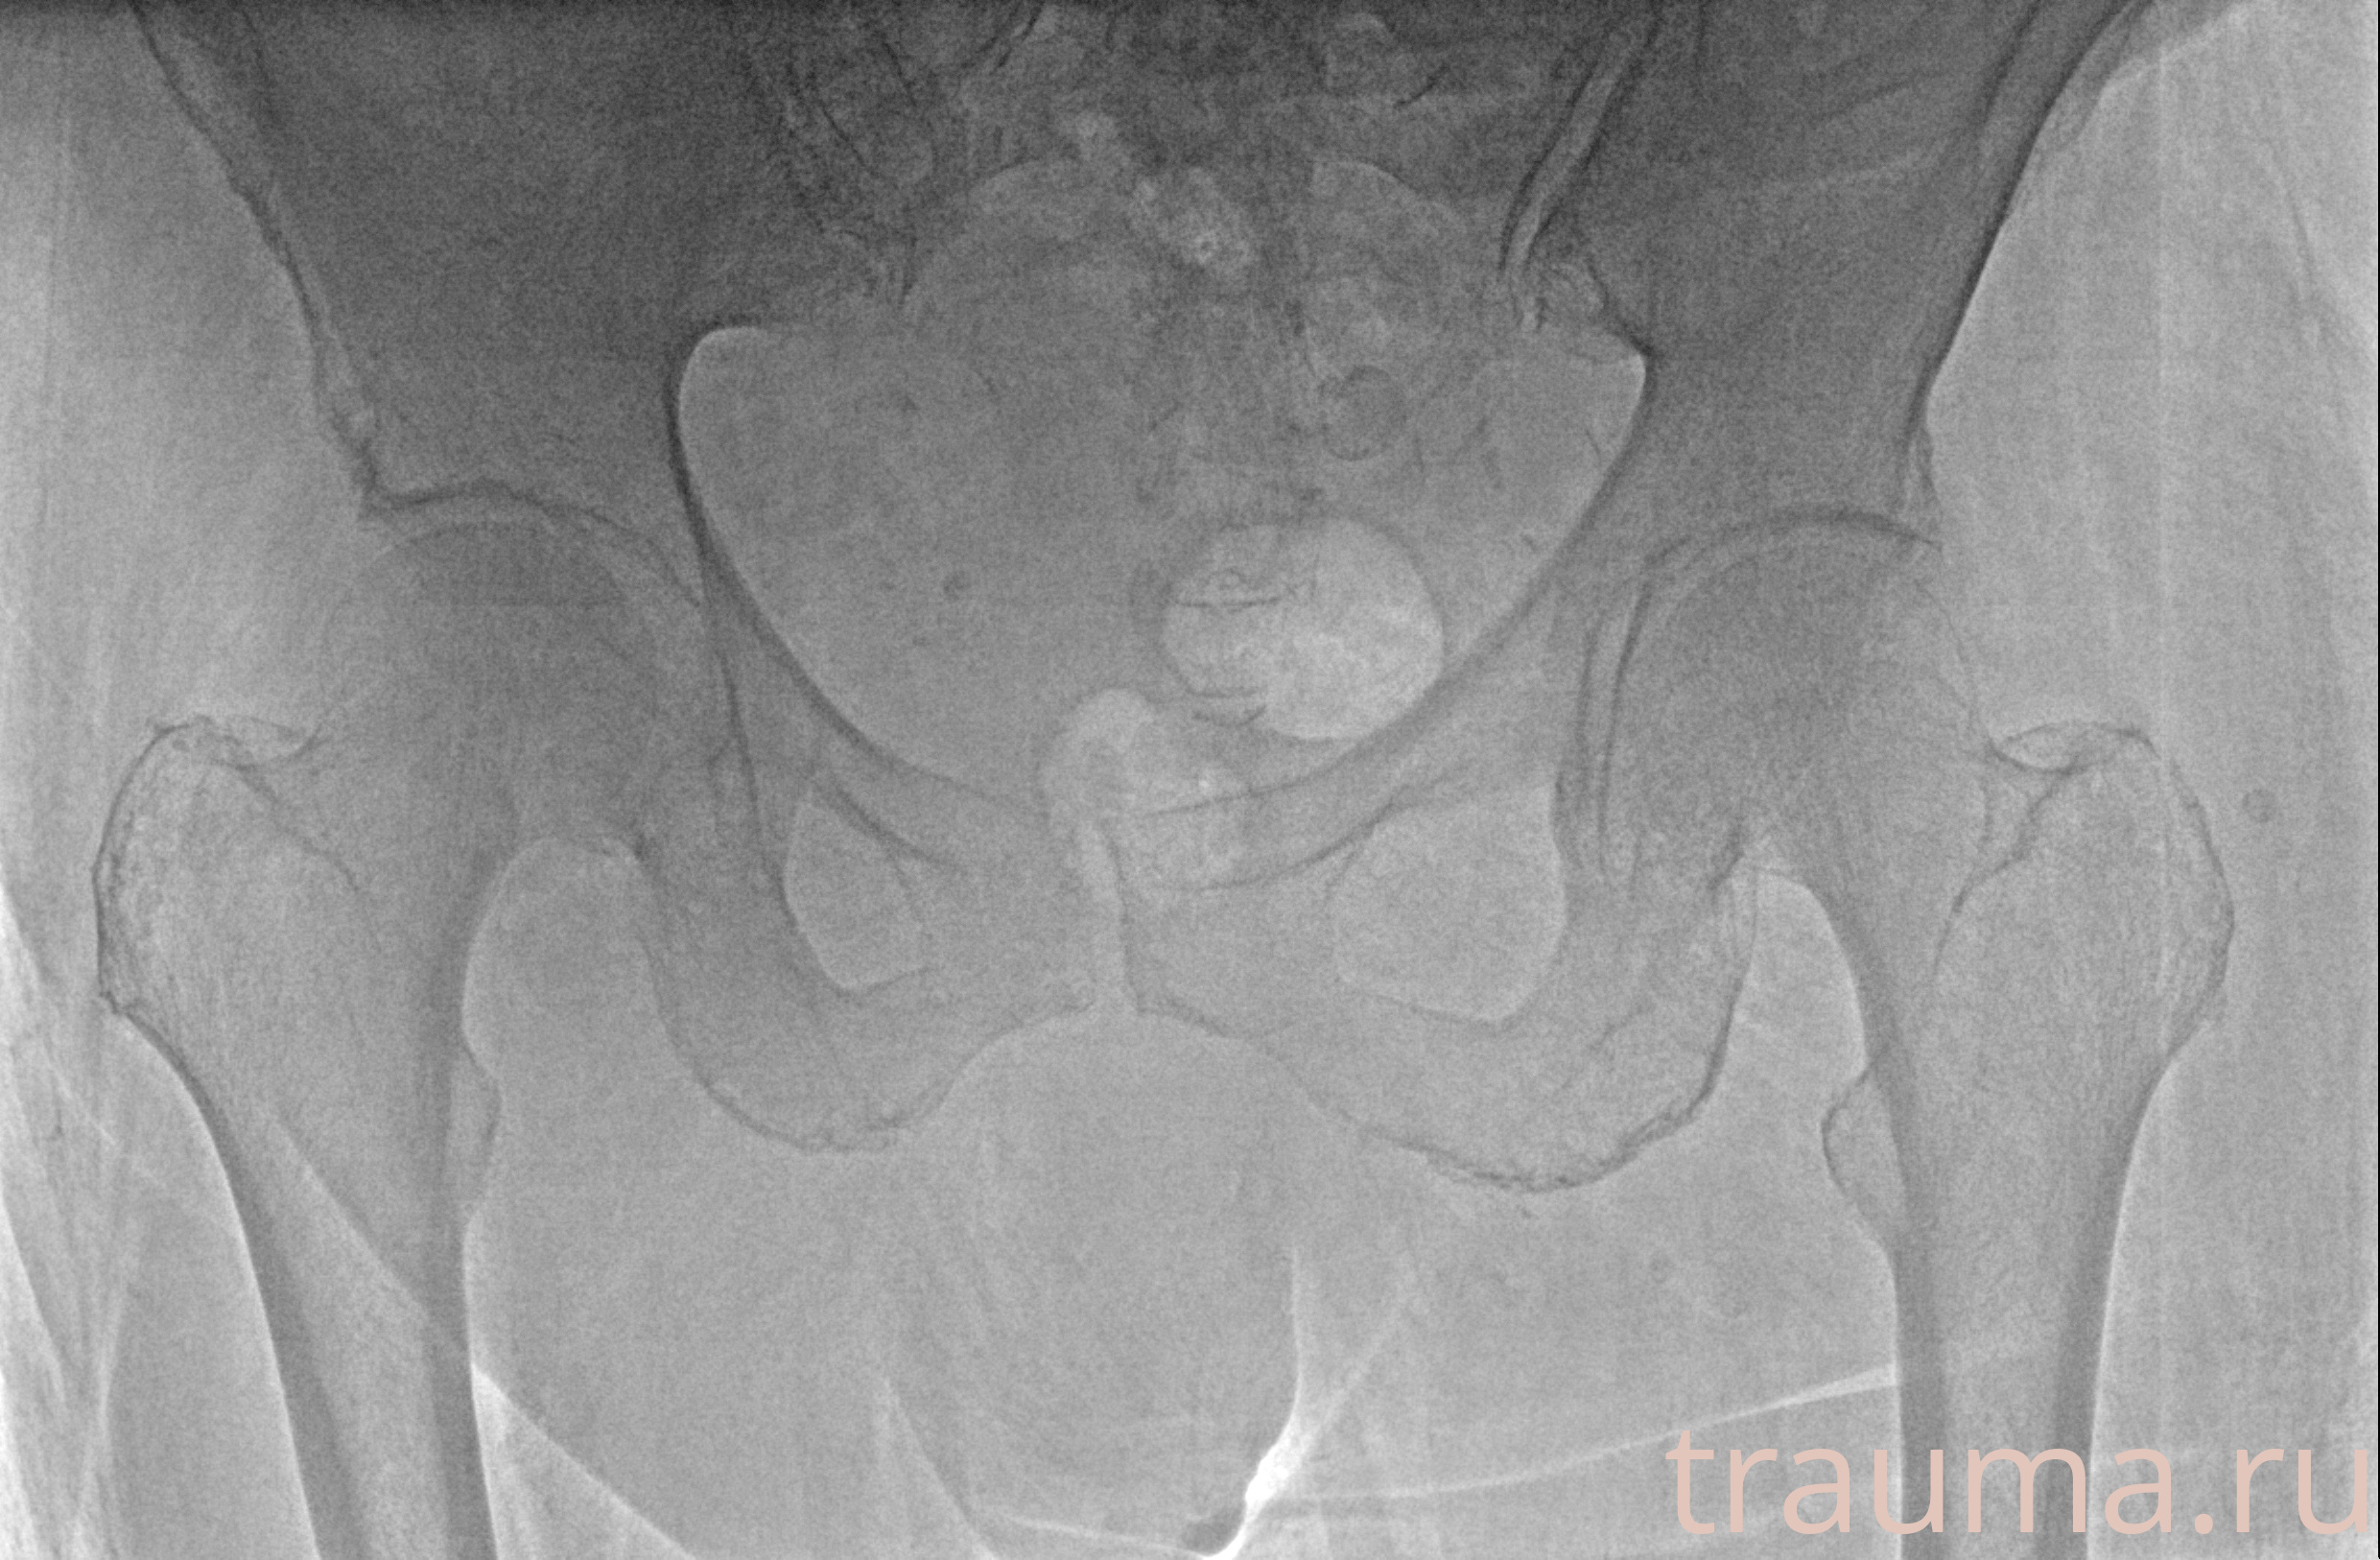

Рентгенограммы

Рентген на дому: по вашему адресу приезжает врач-рентгенолог, травматолог-ортопед с мобильным рентгеновским аппаратом, проводит диагностику травмы или заболевания, делает необходимые рентгенограммы, дает рекомендации по дальнейшему лечению. Получить качественные снимки в домашних условиях возможно благодаря уникальной методике, разработанной МосРентген Центром для института  Склифосовского